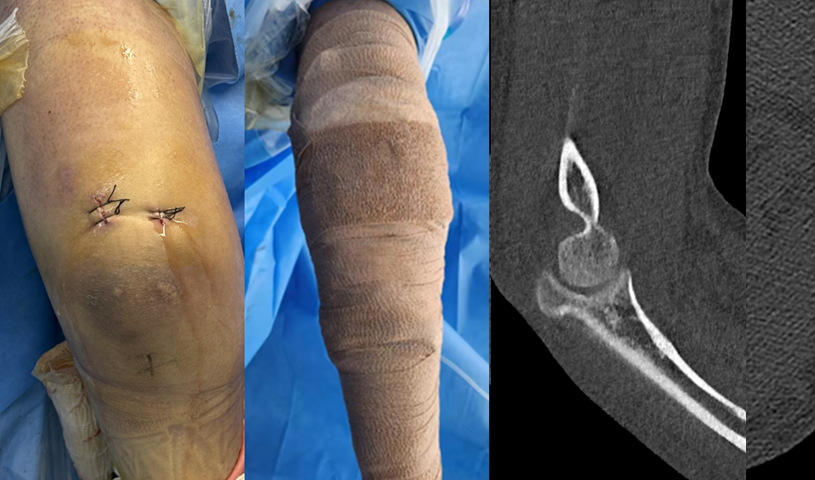

患者朱先生,33岁,1月前骑车摔倒致右肘关节疼痛、肿胀及活动受限,他感到肘关节“伸也伸不直,弯也弯不了”。来到我院查体,右肘关节的活动度只有屈曲90°、伸直30°,活动范围明显受限。术前的影像学检查提示:右尺骨鹰嘴骨折,撕脱的骨碎片游离并卡压于关节间隙。这些“深藏不露”的碎片,正是导致朱先生肘关节持续卡压、活动障碍的“罪魁祸首”。结合病史、查体及影像学检查,诊断为右尺骨鹰嘴骨折伴游离体卡压。

术前CT检查提示关节腔内游离骨折块(红色圆圈)

在医疗团队的精心配合下,于朱先生肘关节后方建立2个毫米级的微小切口,逐一取出多枚软骨碎片,尤其是卡压在肱尺关节深处的一枚较大游离体,这正是造成患者肘关节症状的元凶。手术全程耗时1小时余、出血仅10ml,术后即刻查体:肘关节活动度达伸直0°、屈曲130°,患者苏醒后未见神经血管并发症。目前,患者在骨科及康复医学科团队指导下正积极进行康复训练,有望完全恢复肘关节功能,重返日常的工作生活。

镜下取出多枚游离体,术后CT验证关节腔内游离体已彻底清除